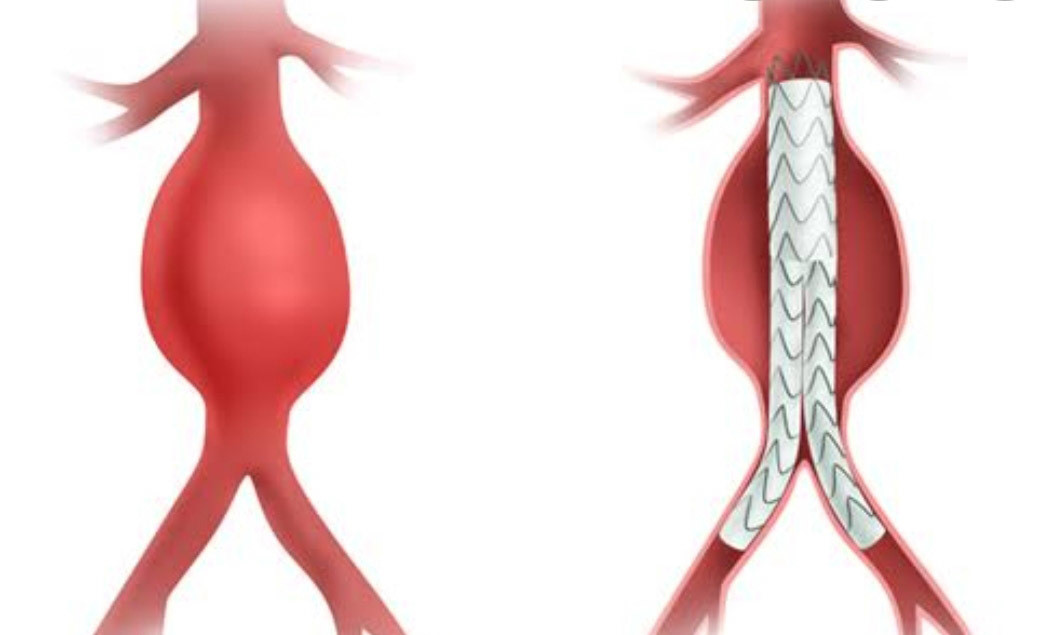

Снимки и иллюстрации микроаневризм сосудов головного мозга